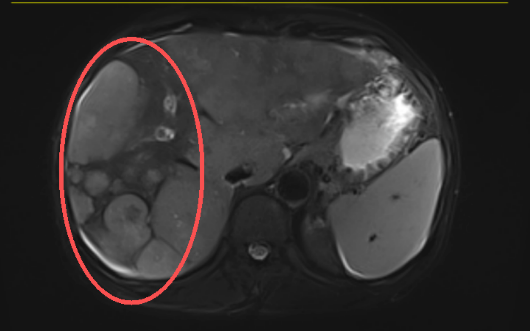

患者张大爷(化名),60岁,因“上腹痛伴腹胀1个月”就诊,最终确诊为原发性肝癌IIIa期,同时合并门静脉癌栓、下腔静脉癌栓、慢性乙型病毒性肝炎,还伴随严重的肝损害、高胆红素血症等多项异常指标。

介入治疗科团队在全面评估患者病情后,制定了个体化的治疗方案:经导管肝动脉造影化疗栓塞术(TACE)。

手术精准阻断肿瘤供血动脉,让肿瘤“饿死”的同时,局部高浓度化疗药物直接作用于病灶,最大程度减少对全身正常组织的损伤,尤其保护了本就脆弱的肝功能。术后,团队同步给予保肝、抑酸等支持对症治疗,全程精细化管理患者的各项指标。